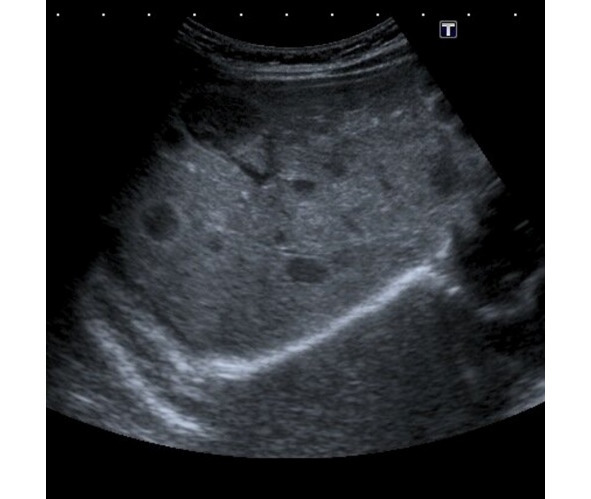

Fig. 20 Ultrasound examination of multiple hemangioma of the liver. Multiple round foci of reduced echogenicity are noted.